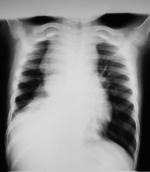

Jak doszedłem do prawidłowej diagnozy